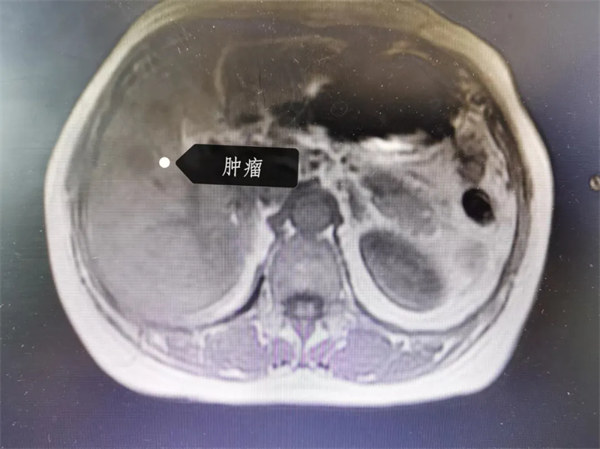

明確診斷患者為原發(fā)性肝癌、肝硬化伴食管胃底靜脈曲張、頸椎病、睡眠障礙、焦慮抑郁狀態(tài)、慢性丙型病毒性肝炎、腎上腺腺瘤、后循環(huán)缺血。肝膽胰脾外科多次組織討論會(huì)、MDT研究患者病情,探究適宜治療方案,考慮到患者一方面長(zhǎng)期肝硬化,肝臟功能受損嚴(yán)重且既往因肝硬化脾大曾行脾臟切除術(shù);另一方面更嚴(yán)峻的情況是,此次發(fā)現(xiàn)的肝癌位于肝右葉的5段,瘤體位緊鄰肝右靜脈與肝內(nèi)右前肝蒂主干,并且和肝臟6,7,8段位置均較近,患者肝臟儲(chǔ)備功能差的,多切一分肝臟,就多一分風(fēng)險(xiǎn)。最終團(tuán)隊(duì)考慮為患者采用手術(shù)機(jī)器人、術(shù)前肝臟三維重建、術(shù)中超聲等強(qiáng)強(qiáng)聯(lián)合的科技手段進(jìn)行手術(shù)。

機(jī)器人具有裸眼3D功能,可通過(guò)高清影像系統(tǒng)和精確的機(jī)械臂,實(shí)現(xiàn)對(duì)肝臟腫瘤的精準(zhǔn)定位和切除。在機(jī)器人的幫助下,醫(yī)生能夠更加清晰、立體的觀察到瘤體與周?chē)M織的關(guān)系,確保在切除腫瘤的同時(shí),盡可能多地保留健康的肝臟組織。同時(shí)結(jié)合術(shù)前肝臟三維重建和術(shù)中超聲技術(shù),動(dòng)態(tài)鎖定瘤體位置,并判斷瘤體與肝內(nèi)復(fù)雜管道的關(guān)系。

手術(shù)過(guò)程中,醫(yī)療團(tuán)隊(duì)密切合作,精確控制機(jī)器人的操作,通過(guò)肝外阻斷右前肝蒂的方法確定預(yù)切除肝段的左右分界,通過(guò)術(shù)中超聲找到肝內(nèi)右前肝蒂作為切除肝臟5段的上界, 在全程完整顯露肝右靜脈的基礎(chǔ)上,經(jīng)過(guò)數(shù)小時(shí)的緊張手術(shù),肝膽胰脾外科成功地為患者切除了肝5段,既完整切除了瘤體,保留了一定的切緣,又完整保留了肝右靜脈和右前肝蒂主干,最大程度的保留了足夠剩余肝體積以維持肝臟的正常功能。術(shù)后患者恢復(fù)良好,一周治愈出院。